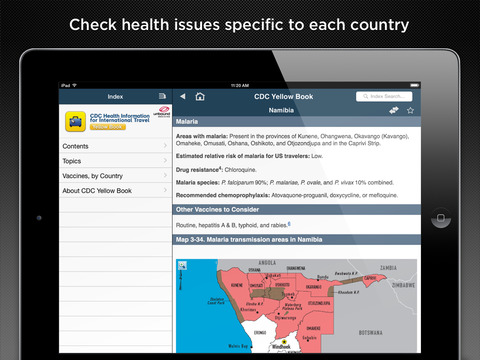

CDC YELLOW BOOK (Health Information for International Travel)

The Yellow Book presents advice on any travel health issue including vaccinations, essential trip planning and safety tips, prevention of an expanded list of travel-related infectious diseases, altitude illness, motion sickness, sunburn, medical tourism, and much more.